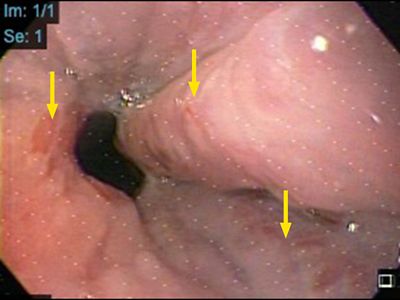

An upper digestive endoscopy was performed and revealed the presence of large esophageal varices (Figure 3), which is correlated with the high values of splenic stiffness.

Figure 3: Image of endoscopy performed on the patient, demonstrating large esophageal varices.